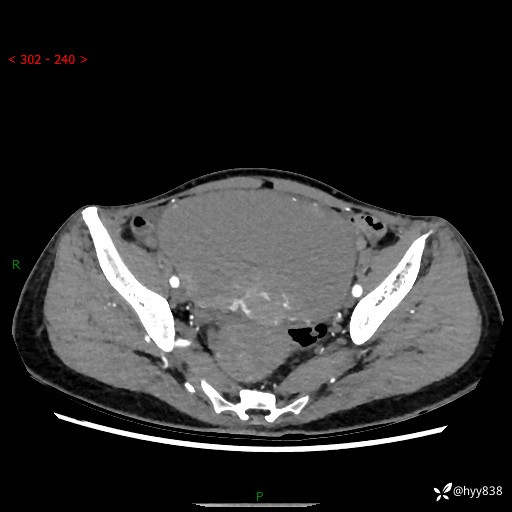

【患者信息】:女,50岁

【主诉】:外院超声发现腹盆肿块,为进一步诊治来我院,门诊已“盆腔肿块”收入院。

腹盆CT平扫+增强

【临床诊断】:盆腔肿瘤